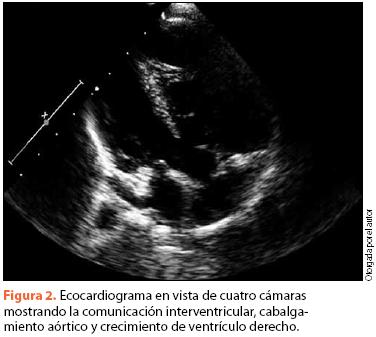

Se procedió a realizar un ecocardiograma, en el que se encontró hipoplasia del anillo pulmonar, estenosis pulmonar mixta de predominio valvular, comunicación interventricular subarterial de 6.7 x 8.8 mm, ventrículo derecho hipertrófico, rama derecha de la arteria pulmonar hipoplásica, cabalgamiento aórtico del 40% y FEVI de 73% (figura 2). Se realizó también tomografia computada, en la cual se corroboró la estenosis pulmonar y se observó dilatación de la aorta ascendente, persistencia de vena cava superior izquierda y disminución en el diámetro de la rama pulmonar derecha (figura 3).

El apoyo en estudios de imagen permite corroborar el diagnóstico y estadificar la gravedad de la enfermedad. Nuestro paciente presentó los hallazgos relevantes en la radiografía de tórax, con un corazón con silueta en de zueco o bota, por levantamiento de punta de VD16. En el EKG se encuentran típicamente datos de crecimiento de cavidades derechas y desviación del eje QRS a la derecha. El ecocardiograma es el método de imagen más útil para confirmar el diagnóstico, al permitir observar los datos de comunicación interventricular, crecimiento de cavidades, estenosis pulmonar y aorta cabalgada. Se han obtenido buenos resultados diagnósticos con el uso de ecocardiografía en etapa fetal, permitiendo obtener datos de alteraciones cardiacas y anomalías asociadas en el feto, además de aportar datos útiles para valoración prequirúrgica17.